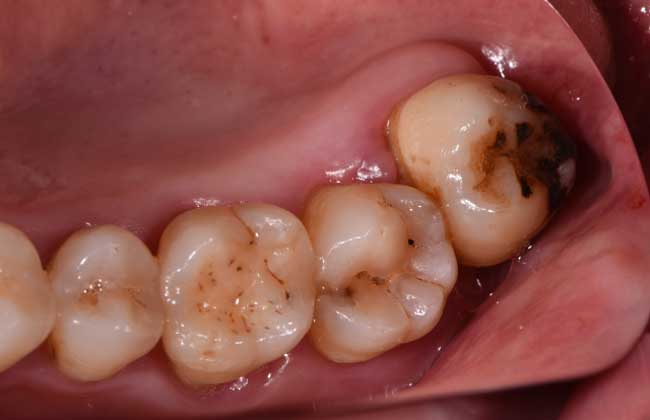

3、第二磨牙龋坏:向前倾斜的阻生智齿,因经常在邻牙间积存食物,易发生邻牙龋坏。